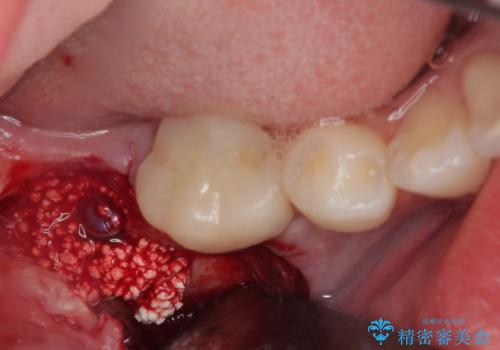

埋伏している右下第二大臼歯は、牽引して咬合に参加させることで計画しましたが、癒着などにより移動困難な場合には、抜歯の上インプラント補綴治療を行うこととしました。

右下の埋伏歯はやはり癒着しており、抜歯の後にインプラントを埋入することとなりました。

埋伏歯の牽引や、奥歯の咬み合わせ改善、インプラント補綴治療と治療期間が延びてしまう要素が多く、治療は難航しましたが、最終的に非常に満足のいく仕上がりとなりました。